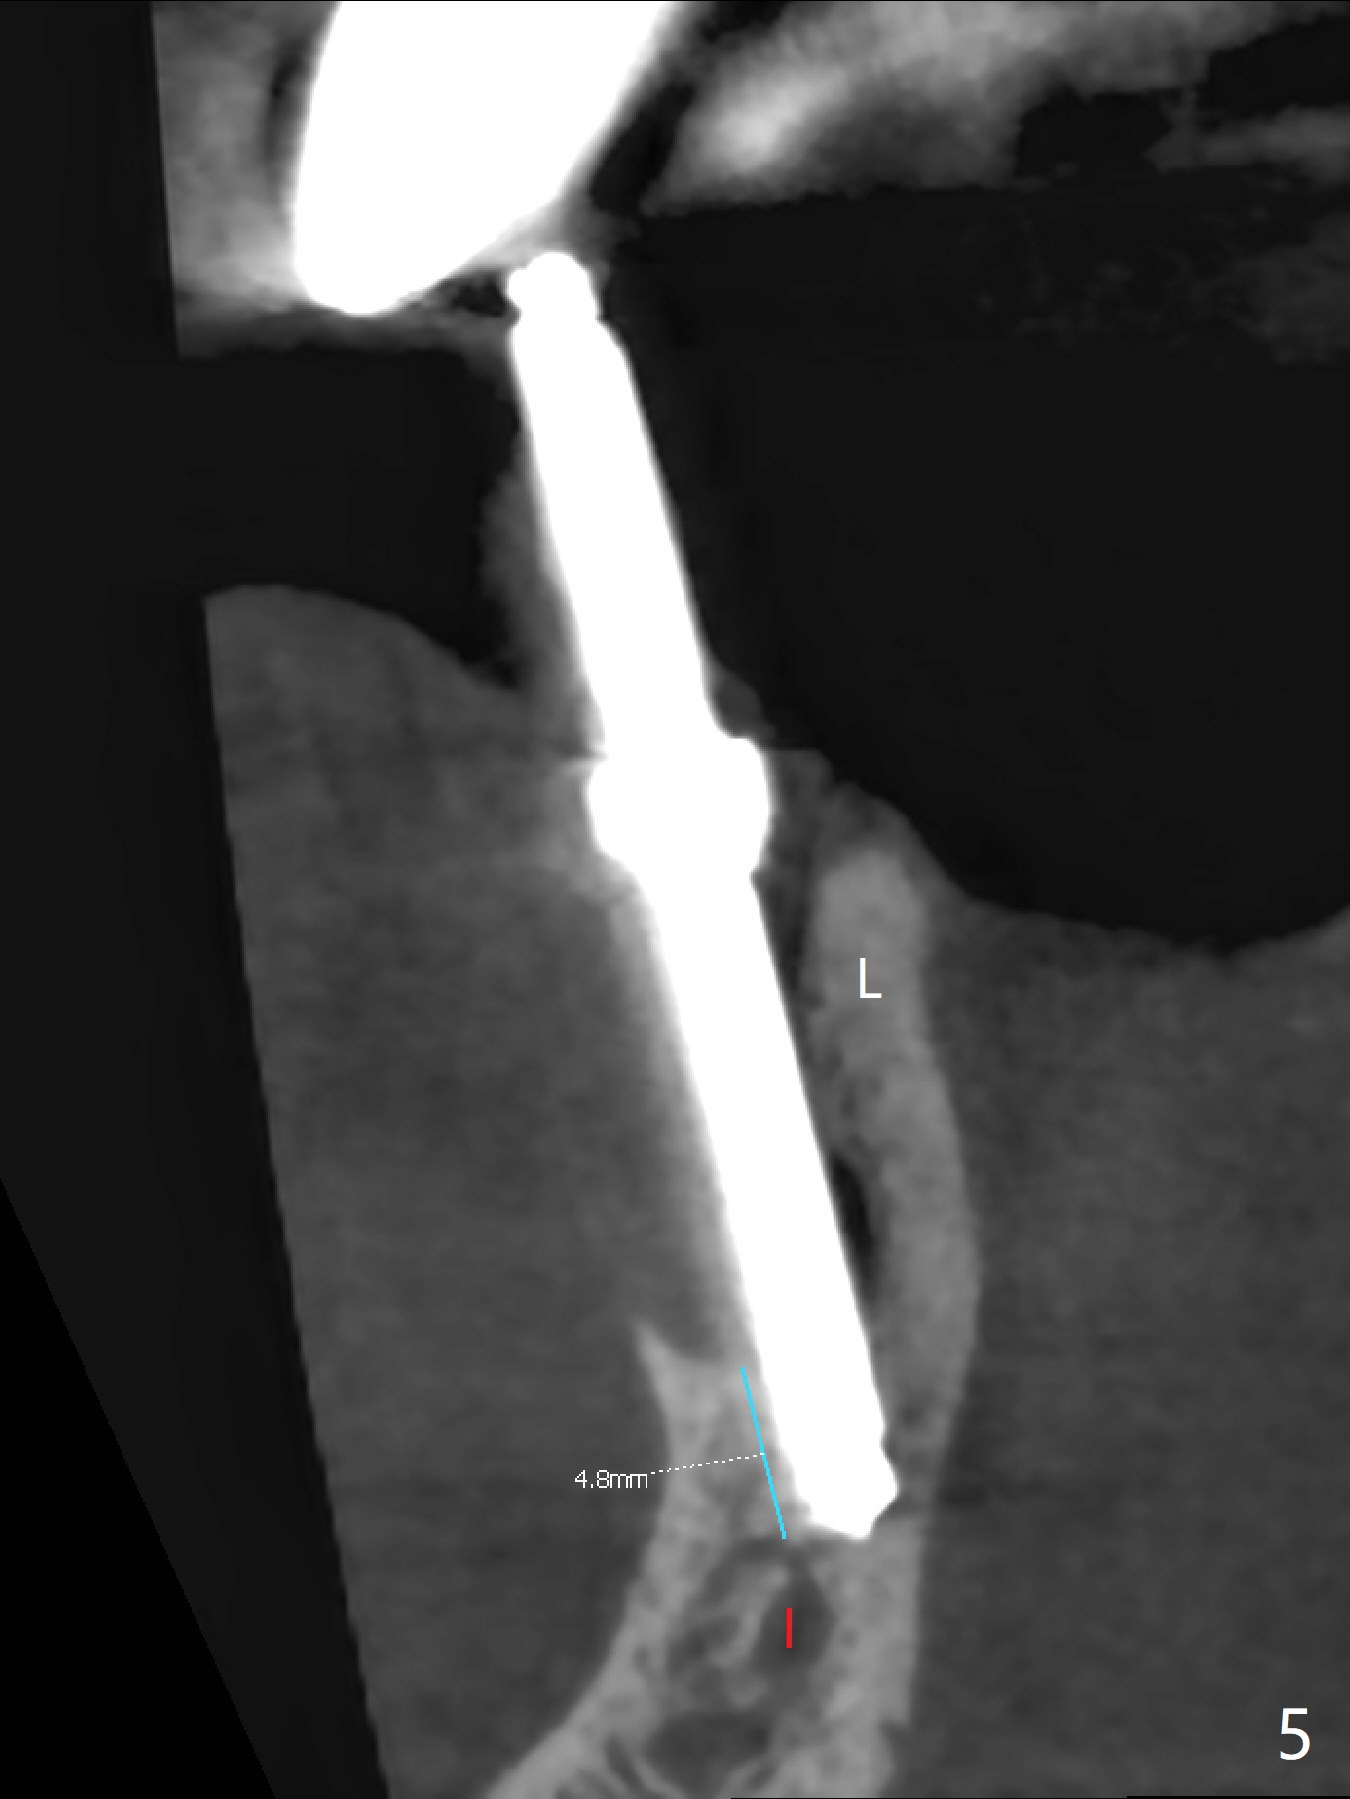

After removal of the split residual roots at #22 (Fig.1), the buccal wall is found to be defective, while the coronal portion of the lingual one (Fig.2 L) is confirmed to be more buccal than the apical portion. A vertical slot is made in the coronal portion of the lingual plate (Fig.3 *) in order to establish osteotomy lingual (Fig.4 O). The depth of the osteotomy in the apical native bone is 4.8 mm (Fig.5 CT coronal section). After the final drill (3 mm) is removed, a 3.8x16 mm implant is placed lingually for secure 2-pointed fixation (Fig.6,7, coronally: mesiolinguodistal; apically: in the native bone (Fig.9)). The essence of the lingual placement is the presence of a large buccal gap for Osteogen plug (Fig.8 yellow) and allograft (Fig.8 red, 9,10 (*)) for potential regeneration of the buccal plate. With bone graft and the overlying provisional (Fig.11 P), the buccal plate seems to have been established (*) 1 week postop. There is no obvious implant thread exposure 8 months postop (Fig.12). But the buccal plate is atrophic when the crown is cemented (~10 months postop, Fig.13).